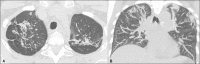

Objective: To describe the relationship between coronavirus disease 2019 (COVID-19) and pulmonary tuberculosis during the current pandemic, as well as to describe the main computed tomography (CT) findings in patients suffering from both diseases simultaneously.

Materials and methods: This was a retrospective, cross-sectional observational study of the chest CT scans of 360 patients with COVID-19, as confirmed by RT-PCR.

Results: In four (1.1%) of the patients, changes suggestive of COVID-19 and tuberculosis were observed on the initial CT scan of the chest. On chest CT scans performed for the follow-up of COVID-19, cavitary lesions with bronchogenic spread were observed in two of the four patients, whereas alterations consistent with the progression of fibrous scarring related to previous tuberculosis were observed in the two other patients. The diagnosis of tuberculosis was confirmed by the isolation of Mycobacterium tuberculosis.

Conclusion: Albeit rare, concomitant COVID-19 and tuberculosis can be suggested on the basis of the CT aspects. Radiologists should be aware of this possibility, because initial studies indicate that mortality rates are higher in patients suffering from both diseases simultaneously.